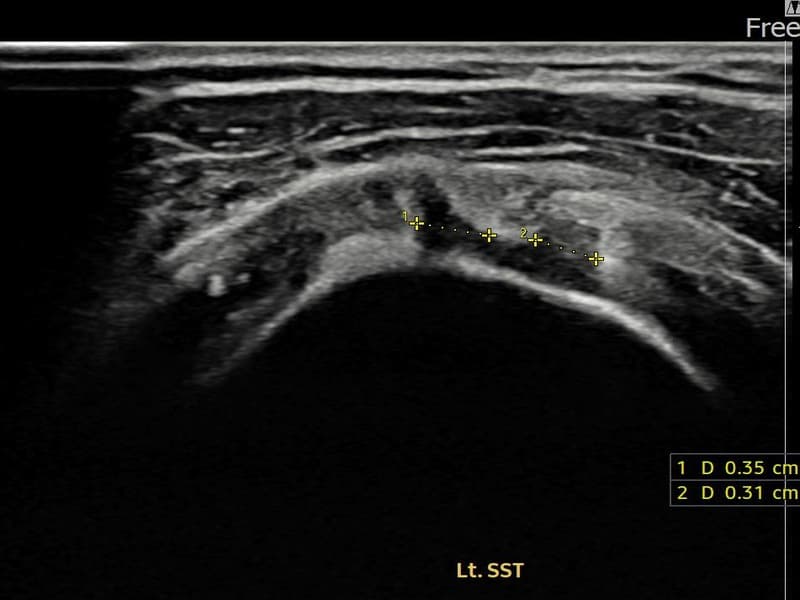

시술 전 초음파 측정 결과 파열 크기는 3.5mm × 3.1mm (부분파열)로 확인되었습니다. 시술 전 초음파에서 좌측 극상근건 관절면측의 에코 단절과 힘줄 결손 소견이 확인되었으며, 파열 크기는 3.5mm×3.1mm로 측정되었습니다. 시술 후 초음파에서 파열 부위가 재생 조직으로 채워지고 힘줄 에코 패턴이 개선된 것이 관찰되었습니다.

50대 후반 여성 환자분으로, 왼쪽 어깨 통증이 수개월 지속되어 내원하셨습니다. 초음파 정밀 검사에서 극상근건 관절면측 부분파열이 확인되었으며, 파열 크기는 비교적 소규모이나 증상이 뚜렷하였습니다. 초음파 유도 하 축소봉합술을 시행하였고, 시술 후 단계적 재활 운동을 통해 회복을 진행하였습니다. 시술 14주 후 추적 초음파에서 파열 부위의 연속성이 회복되고 어깨 기능이 정상화된 것이 확인되어 정상 생활에 복귀하셨습니다.